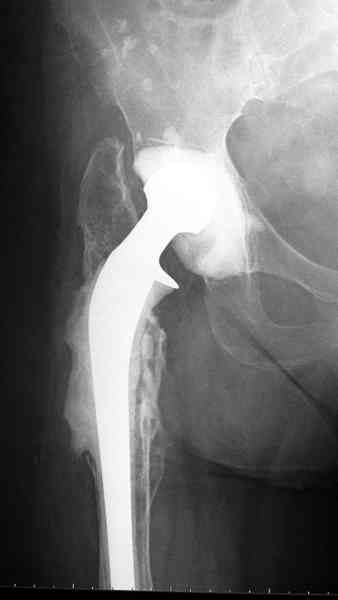

Приглашенный хирург установил ревизионный вариант бедренного компонента без замены ацетабулярного компонента, что осложнилось нагноением и свищами на уровне сустава и средней трети бедра. После двухгодичного безуспешного лечения перевязками и антибиотиками больная обратилась к нам на консультацию.

Повторная операция по удалению тотального протеза с irrigation&debridment, канал после очистки цемента обильно промыт и рассверлен римером.

Приготовлен цемент из расчета: Tobramycin 2.4 g (2 флакона), Vancomycin 2 млн (4 флакона) и 2 упаковки цемента с добавлением дополнительного флакона цементной жидкости.

После обработки ацетабулярного компонента, ещё в мягком цементе в полости вертлужной впадины головкой бедренного компонента сделана выемка для головки, чтобы свежий цемент не прилипал к головке. Головку бедренного компонента завернул обычной стерильной фольгой, которую после образования выемки отлепил от головки.

Для спейсера в бедро использовал старый длинный бедренний компонент меньшего диаметра, облепленный со всех сторон цементом с антибиотиком.

№3-6 снимки с осложнением